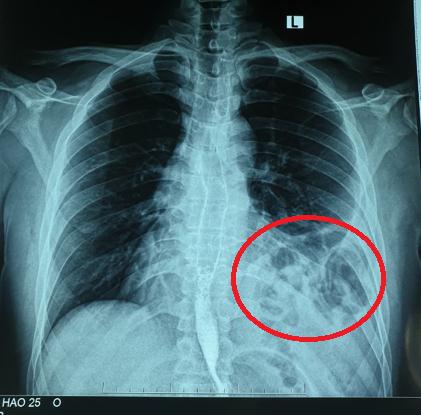

Bệnh nhân Đ.A.H, nam 25 tuổi với tiền sử khỏe mạnh. Hơn một năm trước, bệnh nhân bị tai nạn giao thông xe máy tự ngã, bị đập ngực trái xuống đường. Sau tai nạn, H. thấy đau tức ngực nhẹ, không khó thở nên không đi khám. Trong thời gian tiếp theo, H. thấy cơ thể bình thường khi sinh hoạt lao động nhẹ, chỉ xuất hiện khó thở khi khuân vác các vật nặng. Điều này chưa khiến H. cảm thấy bất thường trong cơ thể mà chỉ nghĩ đơn giản là do làm việc quá sức. Khoảng 5 tháng trước, H. bị mắc Covid-19 tự điều trị tại nhà. Tuy nhiên, sau khi khỏi bệnh, các triệu chứng ho và đau tức ngực vẫn tồn tại và có dấu hiệu nặng lên. Nghĩ mình bị hậu Covid nên H. vẫn tự điều trị tại nhà. Tuy nhiên, mộttháng trở lại đây, H. thấy đau tức ngực kèm ho và khó thở tăng lên. Đoán rằng mình đang có vấn đề về đường hô hấp sau khi mắc Covid-19 nên H. đã đi khám chuyên khoa hô hấp tại Bệnh viện Bạch Mai. Tại đây, H. đã được chỉ định chụp X.quang ngực và được phát hiện có tình trạng có hình bóng hơi của ruột ở trên ngực trái (Ảnh 1). Bệnh nhân được hoàn thiện thêm các xét nghiệm cận lâm sàng và hội chẩn thêm các chuyên khoa, chụp cắt lớp khẳng định có thoát vị tạng bụng qua cơ hoành lên ngực trái. Sau đó, H. được chuyển tới Khoa Phẫu thuật Tiêu hóa – Gan mật tụy để tiến hành phẫu thuật.

Ảnh 1: Bóng khí của đại tràng ở trên ngực trái trên X – quang

– Chụp X.quang: Dấu hiệu mất liên tục vòm hoành, có hình ảnh mức nước hơi của quai ruột trong lồng ngực.